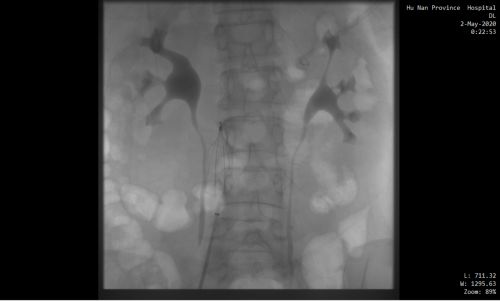

下腔静脉滤器植入前。

下腔静脉滤器植入后。